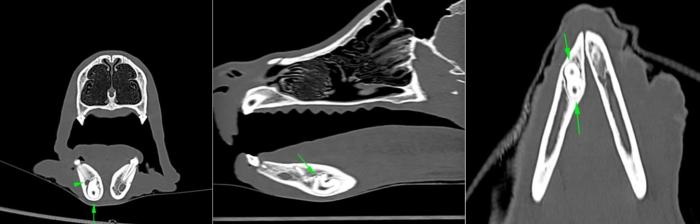

- Presencia del diente 404, incluido en el cuerpo mandibular, ventral a los dientes 406 y 407, con una forma acortada y aberrante (Figuras 5-7).

Tras obtener estos hallazgos, para poder evaluar la posición tridimensional y la relación con las estructuras anatómicas circundantes del diente 404, se recomendó ampliar el estudio mediante la realización de una tomografía computarizada, la cual se programó unos días después en otro centro veterinario.

El estudio tomográfico permitió confirmar el diagnóstico de las alteraciones detectadas (Figuras 8 y 9).

Además, permitió comprobar la relación del diente 404 con los dientes 405 y 406, hallándose este ventral a ellos y al canal mandibular, estando ventral y medial a él. Se observó también que la silueta en la cara medial y ventral de la mandíbula estaba algo engrosada por la presencia del diente.